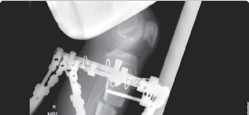

| 49. Two rings per bone segment (near and far) | |||

| 50. Two wires/half-pins per ring | |||

| 51. Four connecting, threaded rods between rings (Figure 15.9) 52. Fibular osteotomy | |||

| 1. Mid-diaphyseal avoids neurovascular structures | |||

| 53. Fix fibula (proximal and distal), to avoid joint subluxation | |||

| Figure 15.9 Radiograph of tibial Ilizarov frame for lengthening. | |||